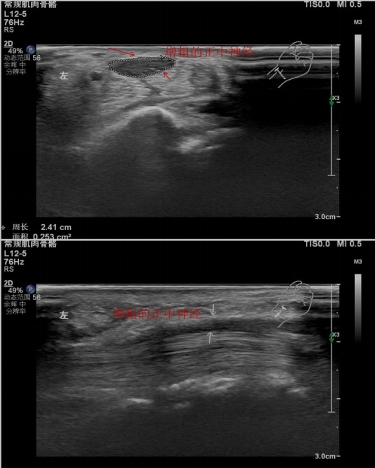

1.腕管綜合征??